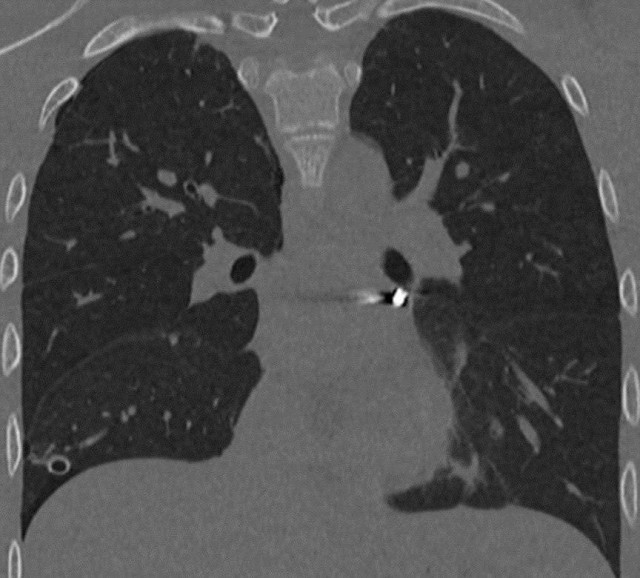

Подросток получил тяжёлое ранение во время игры с пневматикой — пуля прошла всего в нескольких миллиметрах от сердца.

16-летнего подростка доставили в клинику после случайного выстрела из пневматики во время прогулки с друзьями. Пуля попала в грудь и застряла возле сердца, между лёгочными венами у задней поверхности предсердия.

Хирургам удалось извлечь пулю без разреза, работая вблизи жизненно важных структур. Операция прошла успешно, подростка выписали из больницы.

Подросток получил тяжёлое ранение во время игры с пневматикой